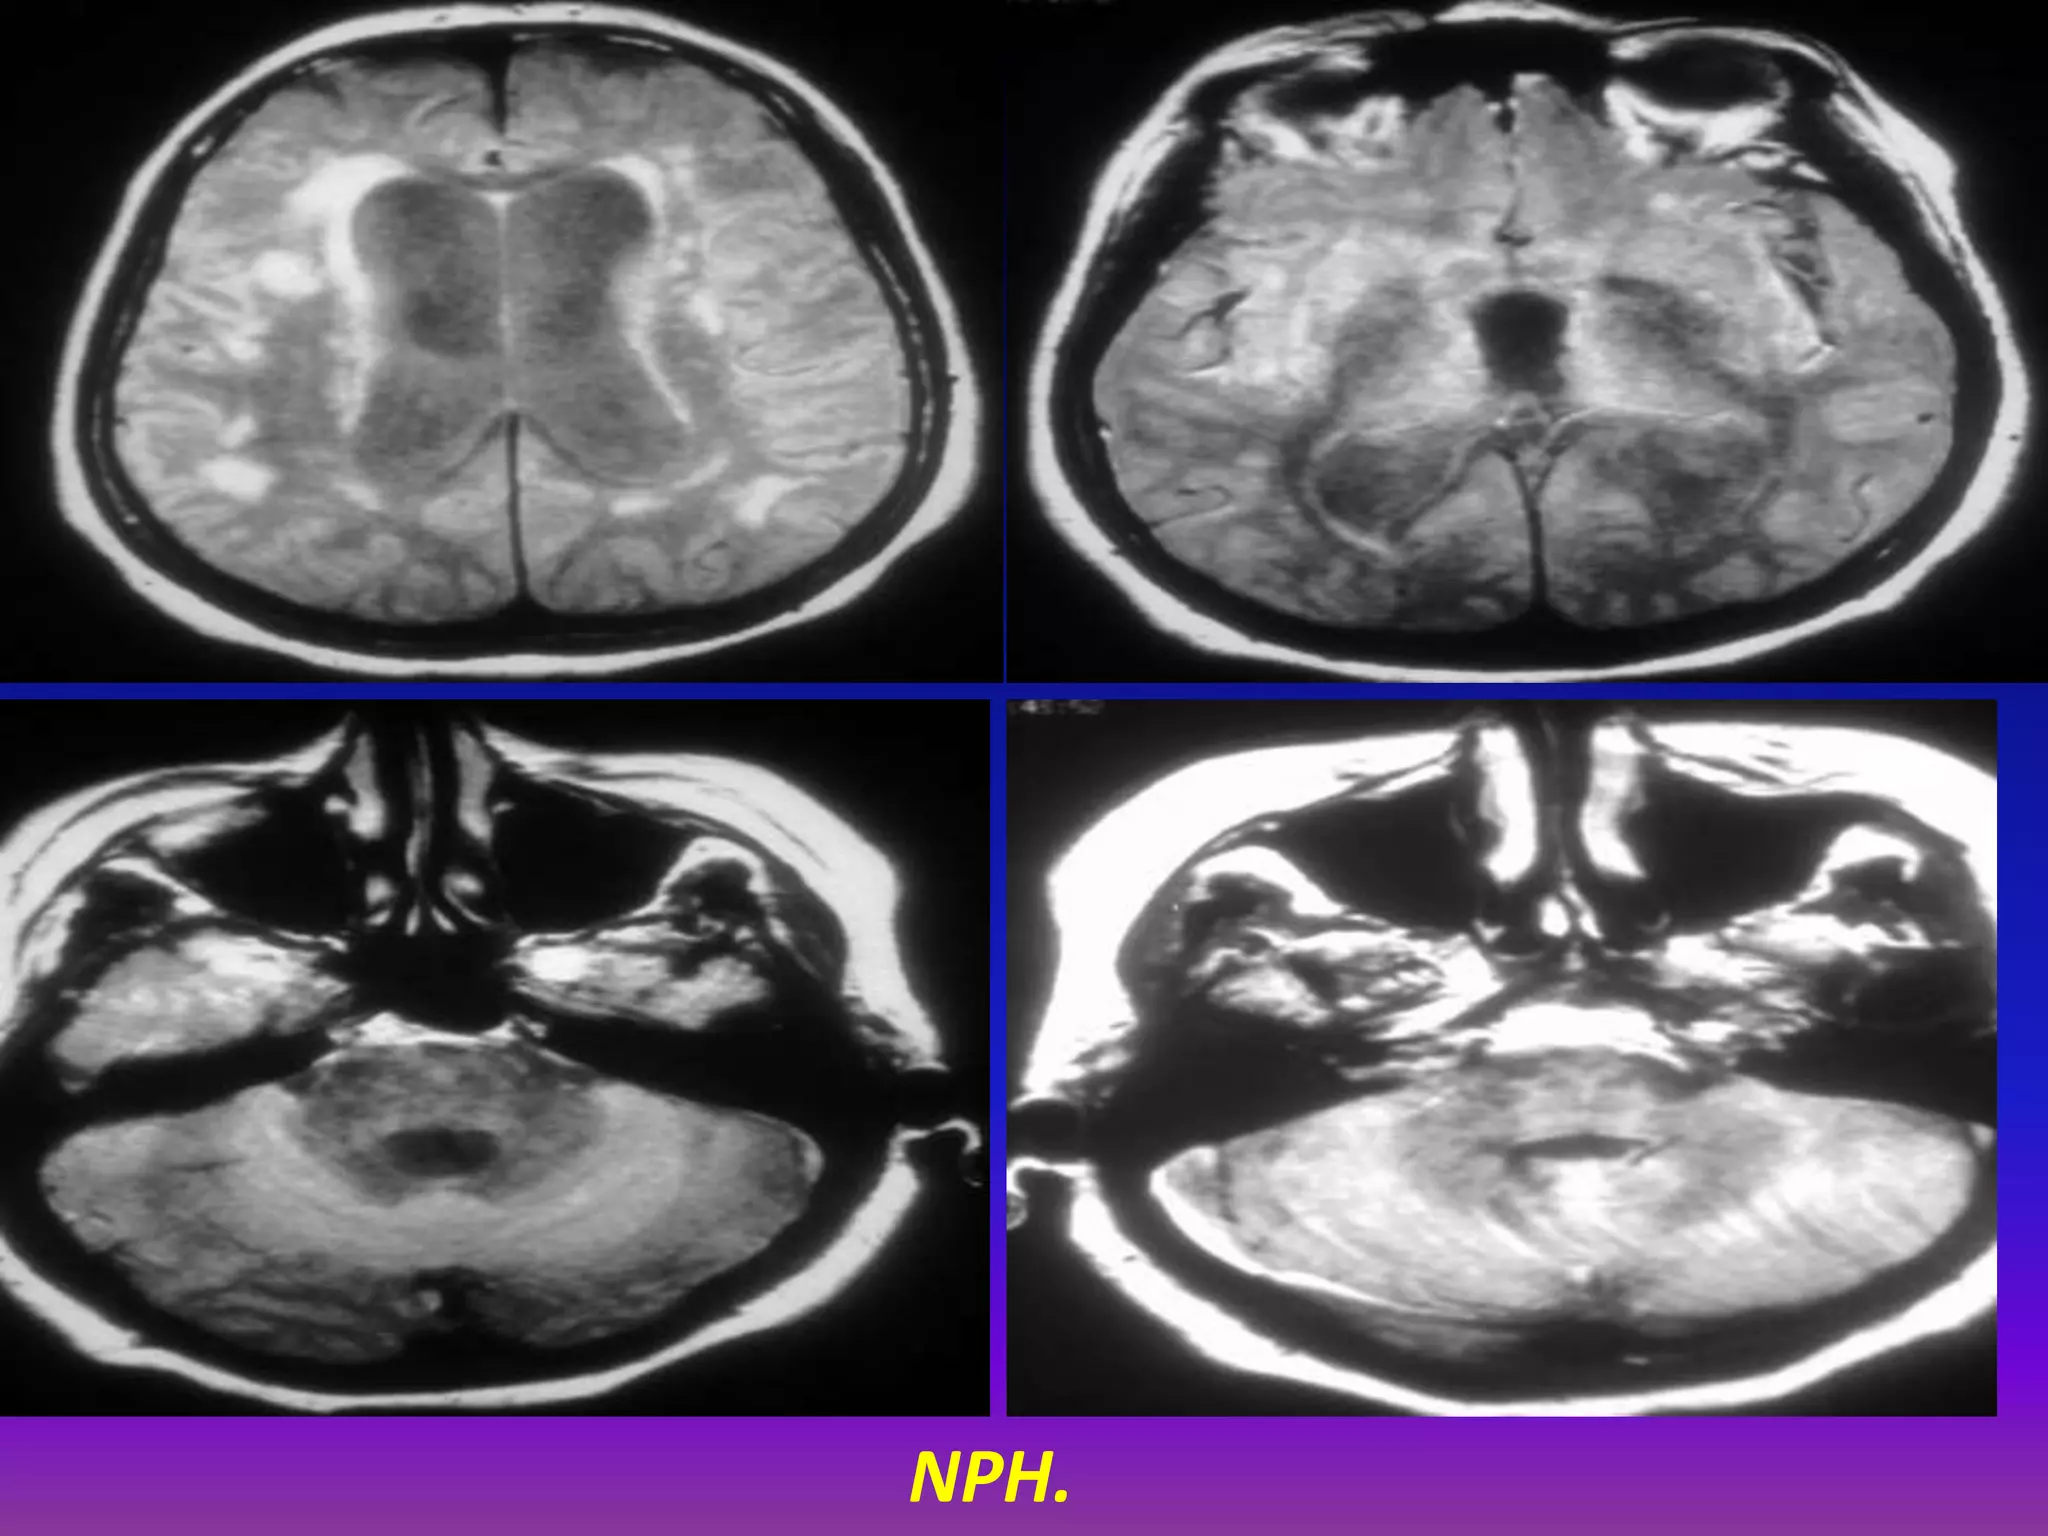

NPH.